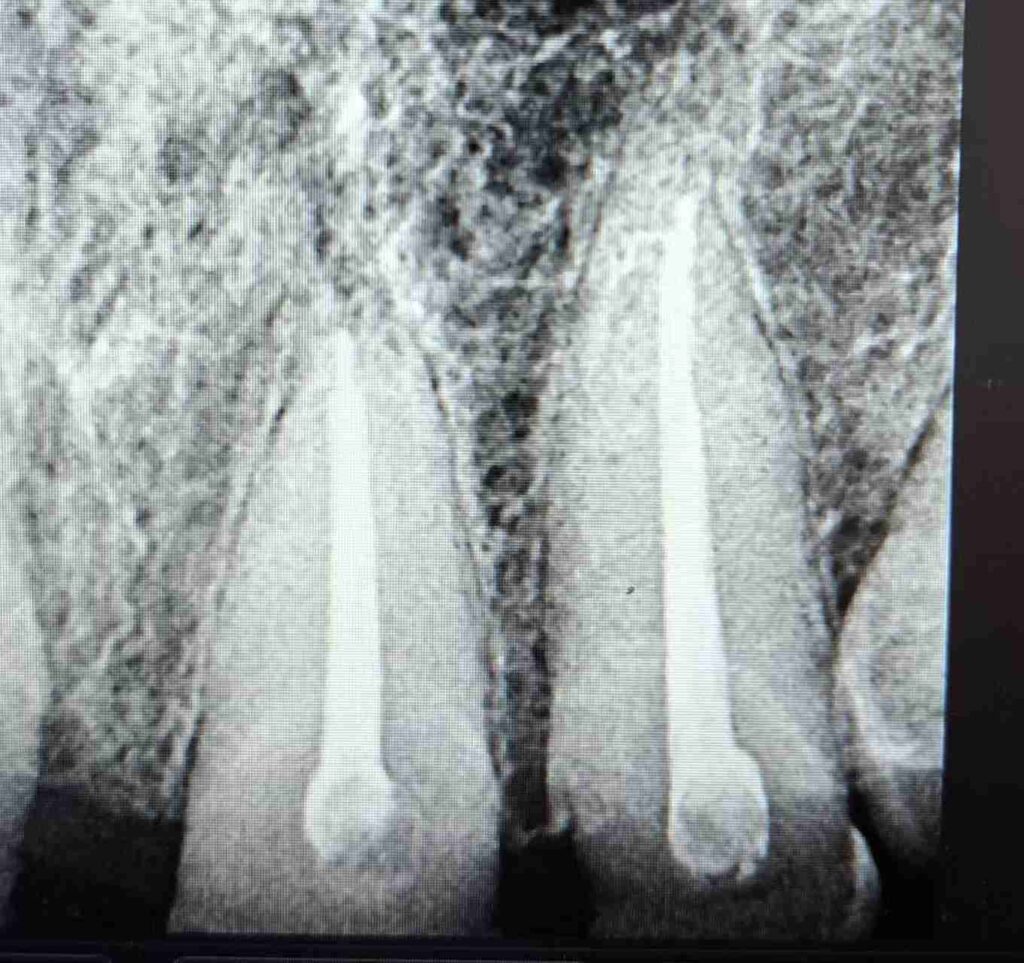

Tras la evaluación clínica y radiográfica detallada, se indicó tratamiento endodóntico en los dientes 11, 12, 21 y 22 con el objetivo de restablecer la salud del sistema de conductos radiculares y crear una base biológica sólida para la posterior rehabilitación protésica del sector anterior.

Durante todo el protocolo se realizaron irrigaciones activas con soluciones desinfectantes, garantizando la eliminación completa de detritos y microorganismos. Finalmente, se completó la obturación tridimensional del sistema radicular, logrando un sellado hermético confirmado por control radiográfico.

- Dientes: #11, #12, #21, #22

- Diagnóstico: Desgaste severo asociado a bruxismo crónico

- Desafío: Endodoncia múltiple simultánea para rehabilitación integral

- Obturación 3D y control radiográfico